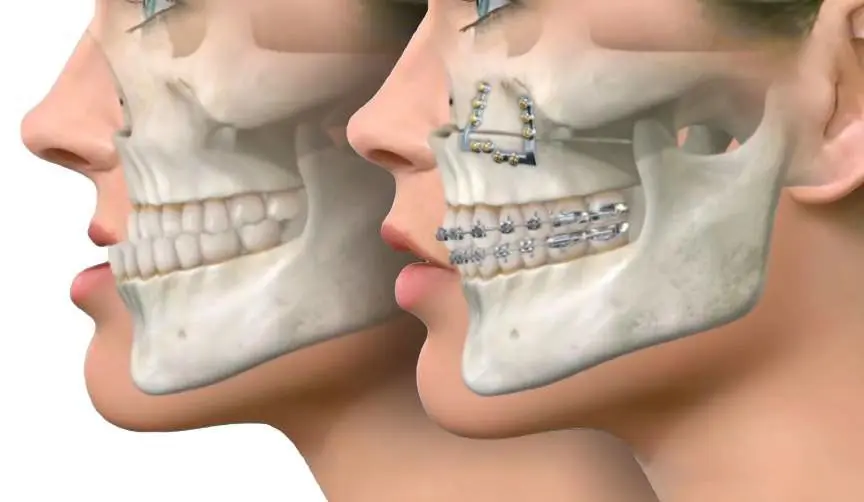

Corrective jaw surgery, also known as orthognathic surgery, is a specialized procedure designed to address irregularities in the jaw bones and realign the jaws and teeth to improve their function. This surgery can be recommended for individuals experiencing difficulties with chewing, speech, breathing, or facial symmetry due to skeletal misalignment. At Ibdaa Dental Clinic, our professional surgeons utilize advanced 3D imaging and precise digital planning to deliver personalized treatments that not only enhance your oral health, but also boost your confidence and facial aesthetics.

Your journey begins with an in-depth consultation and detailed diagnostics, including x-rays and digital scans to assess your jaw structure. The surgical procedure is carried out under general anesthesia and involves repositioning the jaw bones for optimal alignment. Recovery involves a gradual process; most patients resume everyday activities within a few weeks. Throughout your healing process, our team provides continuous support and post-surgery guidance to ensure your comfort, safety, and the best possible results.